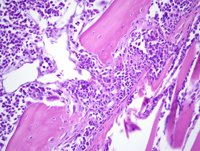

Científicos del Centro de Investigación Médica Aplicada (CIMA) y de la Clínica Universidad de Navarra han descubierto un biomarcador que ayuda a predecir los pacientes con melanoma y cáncer de pulmón con mejor respuesta a la inmunoterapia.

En este estudio se descubre por primera vez un biomarcador dinámico de respuesta a la inmunoterapia, que tiene un potencial abordaje clínico para identificar de modo temprano aquellos pacientes que se puedan beneficiar del tratamiento.

"El estudio, realizado en 29 pacientes con melanoma y 19 con cáncer de pulmón, demuestra que la variación en la concentración de interleukina 8 en el suero de los pacientes predice fielmente la respuesta a la inmunoterapia con anticuerpos monoclonales anti-PD1", explica el doctor Ignacio Melero, investigador de Inmunología e Inmunoterapia del CIMA y de la Clínica Universidad de Navarra, y director del trabajo.